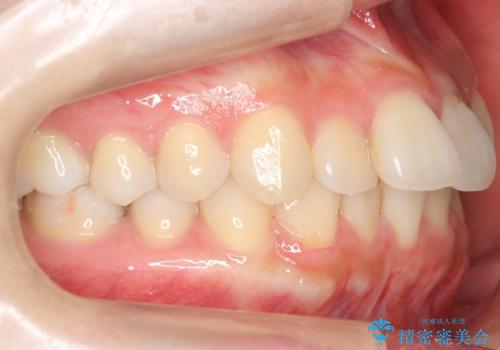

軽度の前歯のがたつき 下の前歯が生まれつき少ない

- 前歯のがたつきを主訴に来院。

下の前歯が生まれつき3本でした。

そのため、上の前歯が少し余るような形で出っ歯になっていたため、スペースを作って引っ込めています。

下を3本でそのまま並べてあるため、上下の正中は合いません。

合わせようとすると抜歯か、下の隙間を無理やり開けてブリッジとなりますが、そこまでするメリットがないため、下はそのままの歯の数を生かしています。